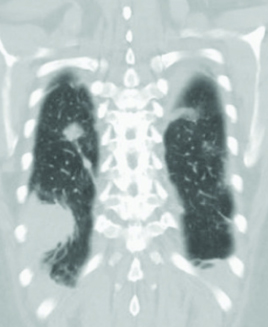

No. 154 症例4:30歳代男性

【画像所見まとめ】

平均年齢は29歳、臨床症状は発熱(90%)、腹痛(67%)、体重減少(50%)。 症状の持続期間は、膿瘍が発見されるまで平均4.7ヵ月。 脾臓が最も多く(71.8%)、リンパ節(50.7%)、皮膚(29.5%)、肝臓(28.1%)、肺(22.5%)。まれな部位は脳、生殖器、腎、頸部、筋、乳房。